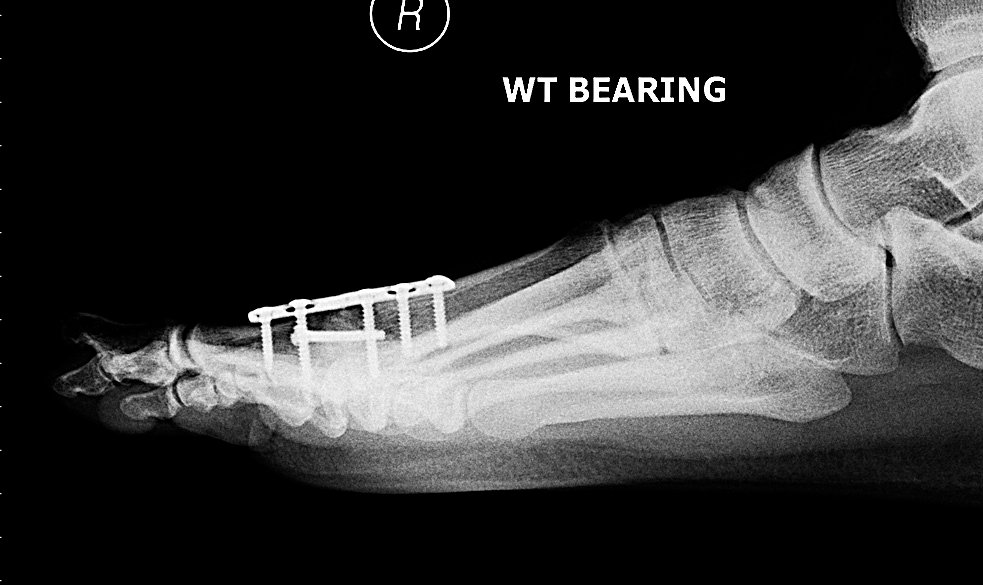

My right foot: completely screwed.

The surgery was successful, with no complications, and within a couple of days I was shuffling around on crutches and wearing a sexy orthopaedic sandal. The actual operation involved cutting away the joint and then sticking the two ends of bone together with a metal plate and some screws. This looks quite dramatic in an x-ray but, since the initial pain of the operation wore off, it’s been completely trouble free.